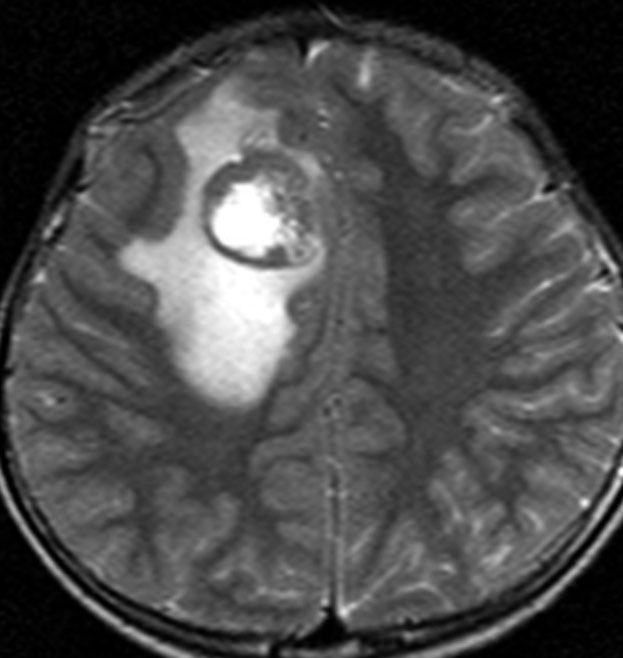

典型的な画像(未分化胎児性腫瘍の組織像を持つもの)

頭痛と嘔吐でみつかった年長児10歳のPNETです。脳外科の先生に上手に手術で全摘出していただいて,すぐに脳脊髄照射25.2グレイ14分割と局所追加照射30グレイ15分割の治療を受けました。その後に相談に来られたので,テモゾロマイド化学療法を24コース追加しました。

腫瘍は消失して元気に学校へ通えています。治療後IQは108あるのですが,右の前頭葉の上前頭回という所に発生したのが幸いであったかもしれません。この場所は確実に摘出できるからです。